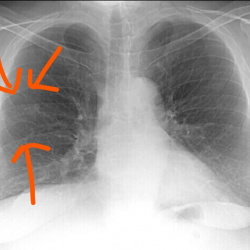

Здравствуйте! Молодой человек пришёл на комиссию, есть ли справа кальцинаты? Также интересует тень на фоне 2 межреберья слева на фоне сосудов - тоже сосуд? Второй снимок выполнен в задней проекции....